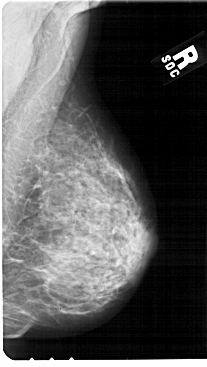

A_1851_1.LEFT_MLO

LEFT_MLO LINES 5476 PIXELS_PER_LINE 2941 BITS_PER_PIXEL 12 RESOLUTION 43.5 OVERLAY

FILE: A_1851_1.LEFT_MLO.OVERLAY

TOTAL_ABNORMALITIES 1

ABNORMALITY 1

LESION_TYPE CALCIFICATION TYPE PLEOMORPHIC DISTRIBUTION SEGMENTAL

ASSESSMENT 4

SUBTLETY 3

PATHOLOGY MALIGNANT

TOTAL_OUTLINES 1

BOUNDARY